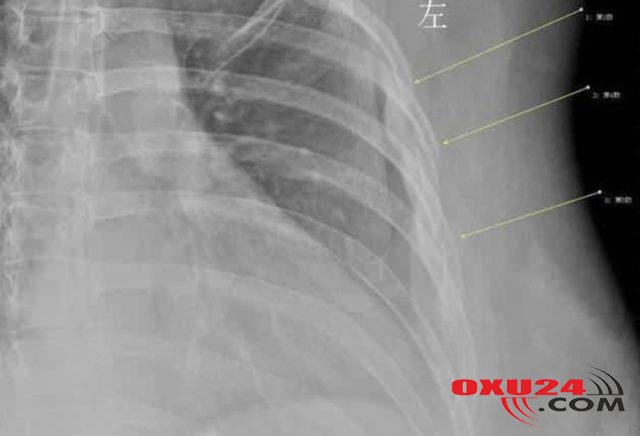

30 yaşında olmasına baxmayaraq sümükləri 60 yaşlı bir qadına sümüyü kimi olub. Çində yaşayan Xan Xiaonun nizamlı bir həyatı vardı və ofisdə demək olar ki, hər gün 10 stəkan qəhvə istehlak edirdi. Üstəlik, Xan, qəhvəsini südsüz və olduqca tünd içməyi üstün tuturdu. Davamlı olaraq işlətdiyi kofe, Xanda fiziki və zehni olaraq asılılıq yaratdı. İrəliləyən zamanlarda yuxu məsələsində ciddi problemlər yaşamağa başlayan gənc qadın, bu dövrdə ciddi bir öskürək tutulmasına yaxalandı. Qripə yaxalanan Xan, 10 dəqiqə boyunca keçmək bilməyən öskürəyə daha çox dözə bilməyərək, həkimə getməyə qərar verdi. Həkim, ağrının səbəbini tapmaq üçün rentgen istədi və əsl problemi orada gördü. Xanın üçüncü, dördüncü və beşinci qabırğalarının şiddətli öskürək səbəbiylə qırıldığını gördü. Doktor 30 yaşlı Xana sümük quruluşunun 60 yaşlı bir qadına bərabər olduğunu dedi. Və Xan təəssüf ki, erkən osteoporoz yolundaydı. Artıq qəhvə istehlakının verdiyi ziyanlardan xilas olmaq istəyən Xan, düzgün qidalanma planına keçid etdi və qəhvə miqdarını minimuma gətirdi. Sonra kalsium və zülal dəstəkli bir pəhrizə başlayıb. Mütəxəssislər sümük əriməsi nöqtəsində qadınları ciddi mənada xəbərdar edir və 45 yaş üstü qadınlar mütəmadi sümük sıxlığı testinə girmələrini təklif edir.